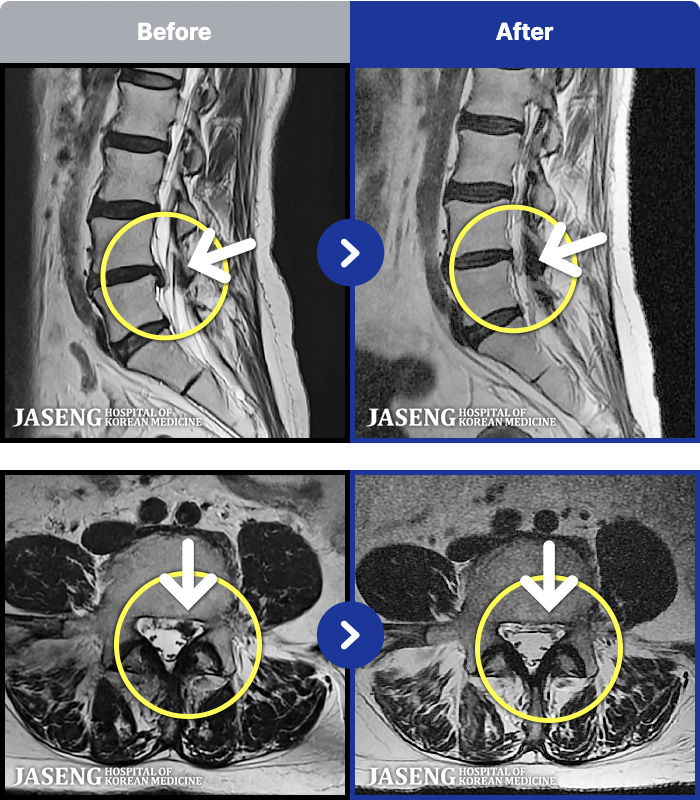

1,268 MRI ũ ʸ Ȯϼ.